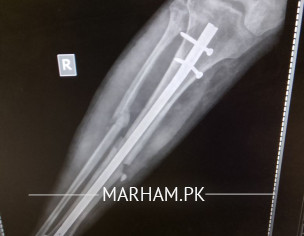

sir mane 5 month pehle opretion keya tha leg ka Lekin mere leg Mai abhi bhi pain ho Raha hai or baghir sahare k nai chal sakta sir plz check my report k Kya reason hai

seems like a case of delayed union. take vit d and calcium supplements and visit orthopaedic nearby. hopefully it will improve.

sir plz reply me k Kya Mai phir opretion karon? q k es Mai haddi ka ik piece hai jes se leg Mai soojan hothi hai or ik keel morh geya hai.plz reply me

Aap ki haddi poori tara se juri nai ay abhi jis ki waja se dard huta ay aapko koi peep waghera aati hai??

sir ye haddi ka Kya karon Jo ik chota sa peace hai